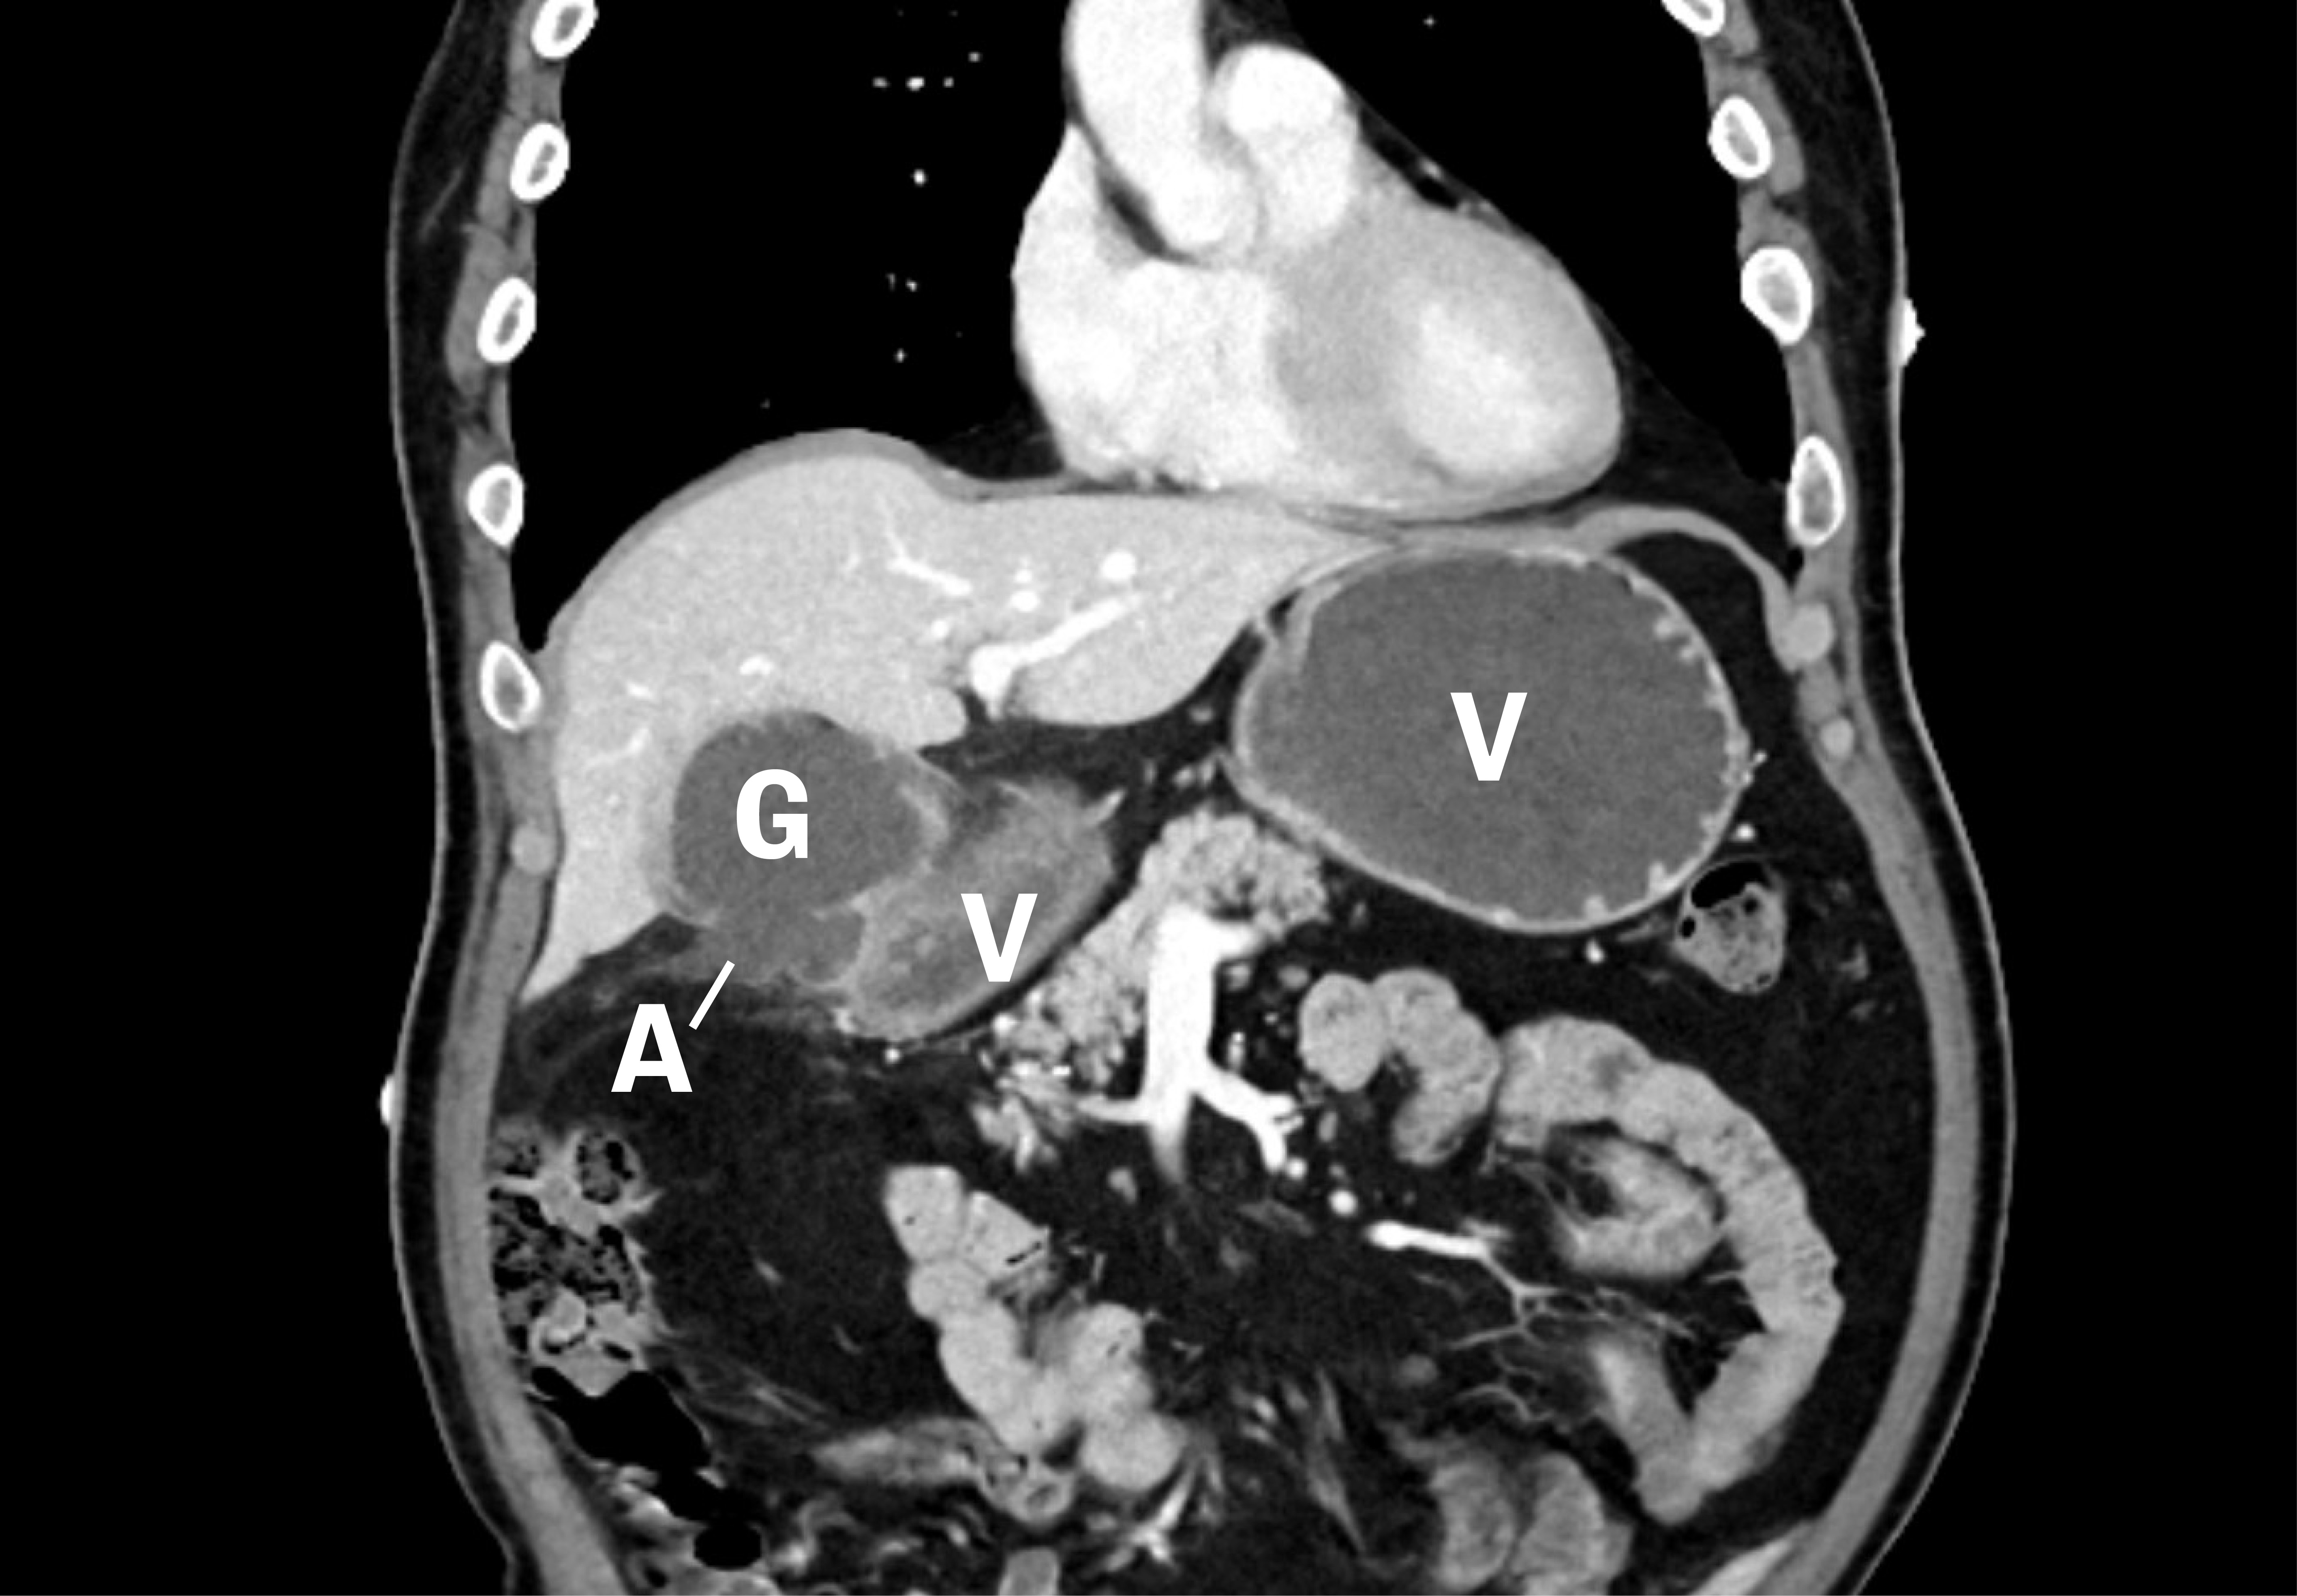

Dag 2 hadde pasienten lett fallende leukocytter 13,9 · 109/L (3,5–10), CRP 41 mg/L (< 4), ALP 120 U/L (35–105) og pankreasamylase 69 U/L (10–65), ellers var tilstanden uendret. Vi vurderte intraabdominal abscess, pankreatitt eller malignitet som aktuelle differensialdiagnoser, og henviste derfor til CT-undersøkelse av toraks og abdomen som viste en veggfortykket galleblære med økt kontrastoppladning, samt en defekt i galleblæreveggen medialt med en væskeansamling på 6,2 × 4,6 cm nær galleblæren og ventrikkel antrum. I tillegg fantes moderate reaktive forandringer i fettvevet rundt, samt noe markert ventrikkelvegg og nærliggende diafragma. Dette ble tolket som en kolecystitt med perforasjon, hvor det var dannet et avkapslet lokulament mellom galleblære og ventrikkel. Dette lokulamentet kommuniserte med galleblæren (figur 1).

Vår kasuistikk illustrerer at vedvarende hikke kan ha en intervensjonskrevende årsak, som en intraabdominal abscess. Nær anatomisk lokalisasjon med reaktive forandringer tett på diafragma, og samsvar i tid mellom galleblæredrenasje og opphørt hikke, taler for at hans perforerte kolecystitt var årsaken til hikken.